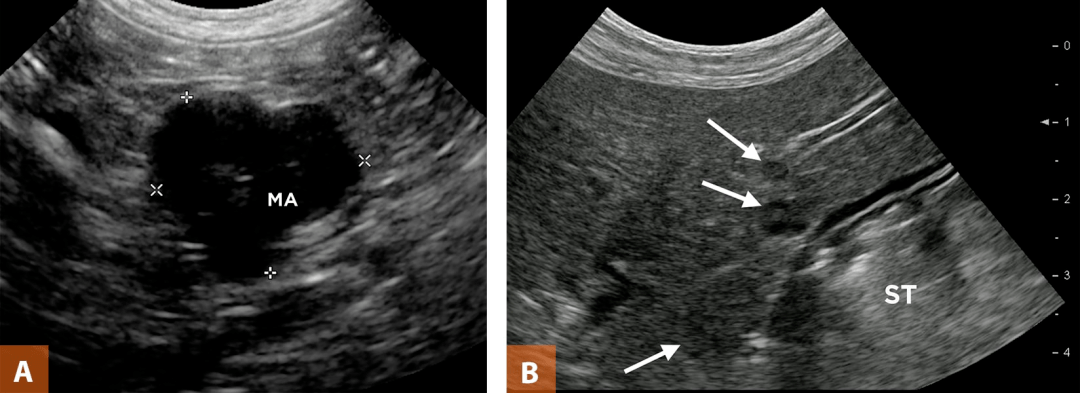

(一) 声像图特征

1.在胰腺癌所在部位的胰腺内出现低回声肿块,边界不整齐,轮廓不清晰,肿瘤常向周围组织呈“蟹足样”浸润。肿瘤较大时,癌瘤中心产生液化、坏死而呈混合性肿块。

图片

2.胰腺癌压迫周围脏器及血管,亦可压迫胆管、胰管引起梗阻。

3.晚期胰腺癌,肝内出现转移性肿瘤,胰腺周围、腹主动脉旁出现转移性淋巴结肿大及腹水。

(右图为胰腺癌肝内转移)

(二) 超声检查的临床意义

超声对于肿块大于1cm并向胰腺外突出的胰腺癌诊断的正确率较高,但对于肿块小于1cm且不向胰腺外突出的胰腺癌,尤其是胰腺钩突癌、胰体、尾癌诊断的敏感性和特异性均较差。虽然如此,但是由于胰头癌在整个胰腺癌中占3/4,而且超声具有灵活简便,无辐射、费用低廉等众多优点,所以仍然是作为诊断及早期胰腺癌筛选的首选方法之一。